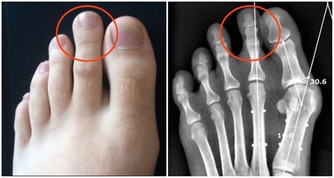

3.血栓45-55歲很容易出現血栓、腦血栓、肺栓塞、心梗等,

抽煙、高血壓、糖尿病、高血脂、久坐不動等都是患血栓的高危因素。

就像水管的水流速度慢,雜質容易沉積一樣。

輕者出現肢體偏癱拄拐等,重者直接威脅生命。

常見症狀

血栓雖然不像癌症那樣症狀比較明顯,但是依然會有一些異樣,

比如,很多腿部靜脈血栓患者前期都會出現“腿疼”,腦血栓患者普遍反映會出現頭痛、偏頭痛等。